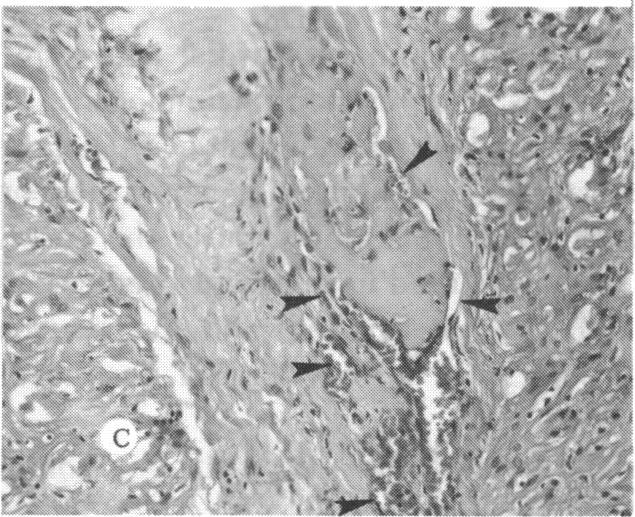

The clinical and histopathologic features of 29 eyes from 29 patients with central retinal vein occlusion (CRVO) are reported. A fresh or a recanalized thrombus was observed in each eye. This study considers the temporal aspects of the cases, and it notes the different morphologic features of the occlusion. These observations explain most of the variability of the changes observed in previous reports. We believe that these different features represent the various stages in the natural evolution of such a thrombus. The interval between CRVO and histopathologic study in our series ranged from six hours to more than 10 years. Local and systemic factors were reviewed and were found to be important in the pathogenesis of thrombus formation. Local diseases with a predisposing effect on CRVO included: glaucoma, papilledema, subdural hemorrhage, optic nerve hemorrhage, and drusen of the optic nerve head. Associated systemic diseases included: hypertension, cardiovascular and cerebrovascular disease, diabetes mellitus, and leukemia with thrombocytopenia. A fresh thrombus in the CRVO was observed in three (10.3%), and a recanalized thrombus in 26 eyes (89.7%). Endothelial-cell proliferation was a conspicuous feature in 14 (48.3%) of the eyes. Chronic inflammation in the area of the thrombus, and/or vein wall or perivenular area was observed in 14 (48.3%) of the eyes. Arterial occlusive disease was observed in seven eyes (24.6%). Cystoid macular edema was found in 26 (89.7%) of the eyes.

报告了29例视网膜中央静脉阻塞(CRVO)患者29只眼的临床和组织病理学特征。每只眼中均观察到新鲜或再通的血栓。本研究考虑了病例的时间因素,并记录了阻塞的不同形态学特征。这些观察结果解释了先前报告中观察到的变化的大部分变异性。我们认为这些不同特征代表了此类血栓自然演变的各个阶段。我们系列中CRVO与组织病理学研究之间的间隔时间从6小时到10多年不等。对局部和全身因素进行了回顾,发现它们在血栓形成的发病机制中很重要。对CRVO有 predisposing 作用的局部疾病包括:青光眼、视乳头水肿、硬膜下出血、视神经出血和视神经乳头玻璃膜疣。相关的全身疾病包括:高血压、心血管和脑血管疾病、糖尿病以及伴有血小板减少的白血病。在CRVO中观察到3只眼(10.3%)有新鲜血栓,26只眼(89.7%)有再通血栓。14只眼(48.3%)中内皮细胞增殖是一个显著特征。14只眼(48.3%)中观察到血栓区域、和/或静脉壁或静脉周围区域有慢性炎症。7只眼(24.6%)中观察到动脉闭塞性疾病。26只眼(89.7%)中发现黄斑囊样水肿。 (注:文中“predisposing”可能是“易患的”意思,但在专业医学语境中,可能有更准确特定含义,这里按常见理解翻译,具体含义需结合医学专业知识进一步确认。)